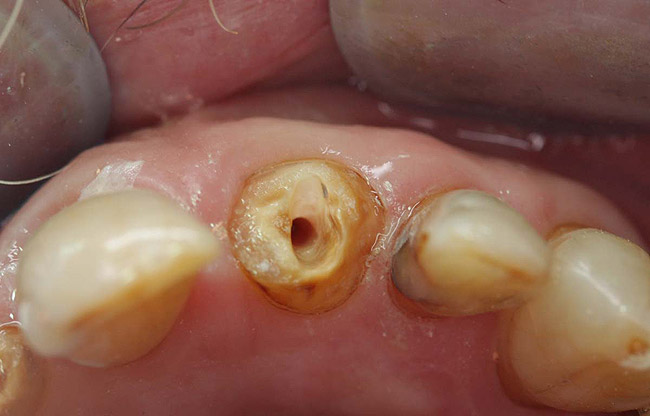

Figure 15  Fractured tooth in a crown of a recently treated endodontically central incisor.

Figure 15

Figure 16  The fractured central incisor root.

Figure 16

A terminally ill patient presented an abscess on the maxillary right central incisor. Endodontic treatment was completed with a composite restoration placed to restore the access hole. The crown fractured off within 1 week (Figure 15 and Figure 16). Gutta-percha was removed, and the canal prepared to accept a C-1 white post (Figure 17). The root was bonded with BRUSH and BOND™ (Parkell, www.parkell.com) and the post was cemented with a resin cement (Figure 18). Absolute Dentin core build-up material was applied (Figure 19). There are many different build-up materials, including glass ionomers such as Ketac-Silver™ (3M ESPE, www.3mespe.com) or Miracle Mix® (GC America, www.gcamerica.com), pastes that are mixed such as Zenith (Carson Dental, www.carsondental.com), and automix syringes such as Absolute Dentin. The material was of a consistency that allows placement without sagging or running (Figure 20). It was light-cured and prepared for temporization (Figure 21) and the final all-composite restoration was delivered (Figure 22).